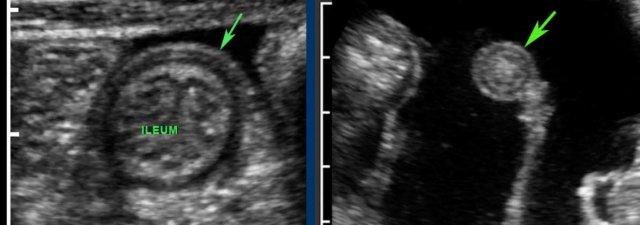

Đây là hình ảnh của hồi tràng tận cùng ở ba trẻ em và người trẻ tuổi khác nhau với các mảng Peyer lớn biểu hiện dưới dạng dày lớp niêm mạc sâu không đối xứng, giảm âm.

Với mỗi kháng nguyên mới, mô bạch huyết lại được tái hoạt hóa.

Ở bệnh nhân trẻ tuổi, cả hạch bạch huyết mạc treo ruột và các mảng Peyer đều lớn hơn nhiều so với người trưởng thành – kể cả về kích thước tuyệt đối.

Mô bạch huyết bị kích thích ở trẻ em không chỉ dẫn đến các mảng Peyer nổi bật ở hồi tràng đoạn cuối và các hạch bạch huyết mạc treo ruột phì đại (hình dưới bên trái), mà còn gây ra tình trạng dày lớp niêm mạc sâu của ruột thừa (hình dưới bên phải).

Lưu ý rằng các phần lồi ra –đôi khi giống polyp- (góc trên bên phải), có thể đóng vai trò là điểm dẫn đầu trong lồng ruột hồi-manh tràng điển hình ở trẻ nhỏ